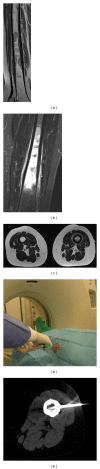

In the management of bone and soft tissue tumors, accurate diagnosis, using a combination of clinical, radiographic, and histological data, is critical to optimize outcome. On occasion, diagnosis can be made by careful history, physical examination, and images alone. However, the ultimate diagnosis usually depends on histologic analysis by an experienced pathologist. Biopsy is a very important and complex surgery in the staging process. It must be done carefully, so as not to adversely affect the outcome. Technical considerations include proper location and orientation of the biopsy incision and meticulous hemostasis. It is necessary to obtain tissue for a histological diagnosis without spreading the tumor and so compromise the treatment. Furthermore, the surgeon does not open compartmental barriers, anatomic planes, joint space, and tissue area around neurovascular bundles. Nevertheless, avoid producing a hematoma. Biopsy should be carefully planned according to the site and definitive surgery and should be performed by an orthopedic surgeon with an experience in musculoskeletal oncology who will perform the definitive surgery. Improperly done, it can complicate patient care and sometimes even eliminate treatment options. Different biopsy techniques are suitable: fine-needle aspiration, core-needle biopsy, and incisional biopsy. The choice of biopsy depends on the size, the location of the lesion, and the experience of the pathologist.